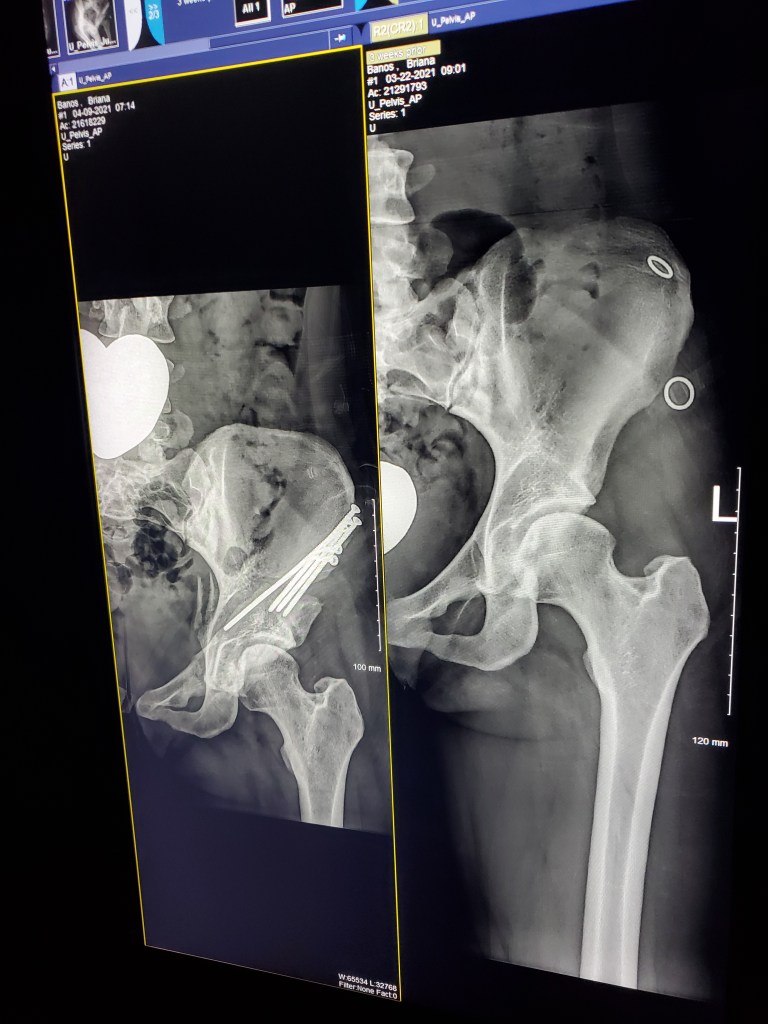

It’s now been 5 weeks since my first arthroscopy surgery and 3 weeks since my PAO surgery.

But let’s cut to the chase… who wants to see the money pics!! Screws and all!